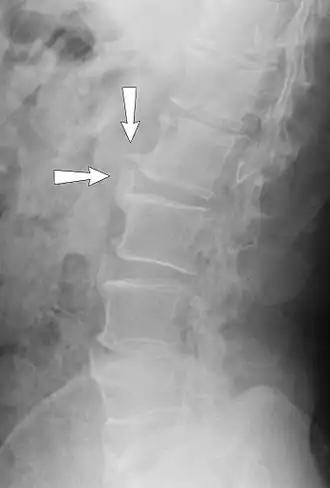

Спондилёз (spondylosis; греч. «spondylos»- позвонок; син. деформирующий спондилёз) — инволюционный процесс постепенного изнашивания и старения анатомических структур позвоночника, сопровождающийся дистрофией наружных волокон передних или боковых отделов фиброзного кольца, выпячиванием его под давлением сохранившего свой тургор мякотного ядра, отложением и оссификацией передней продольной связки и образованием краевых костных разрастаний (остеофитов) вдоль оси позвоночника только по окружности передних и боковых отделов.

При спондилёзе костная ткань суставов разрастается, образуются остеофиты, то есть дополнительная костная ткань (по мере нарастания костный вырост распространяется к соседнему позвонку, тогда как от соседнего позвонка образуется такой же вырост, в некоторых случаях окостенение начинается на уровне межпозвоночного диска). В особо тяжёлых случаях наступает сращение позвонков, от чего страдают сосуды, нервы и мышечная ткань, а также близлежащие органы.